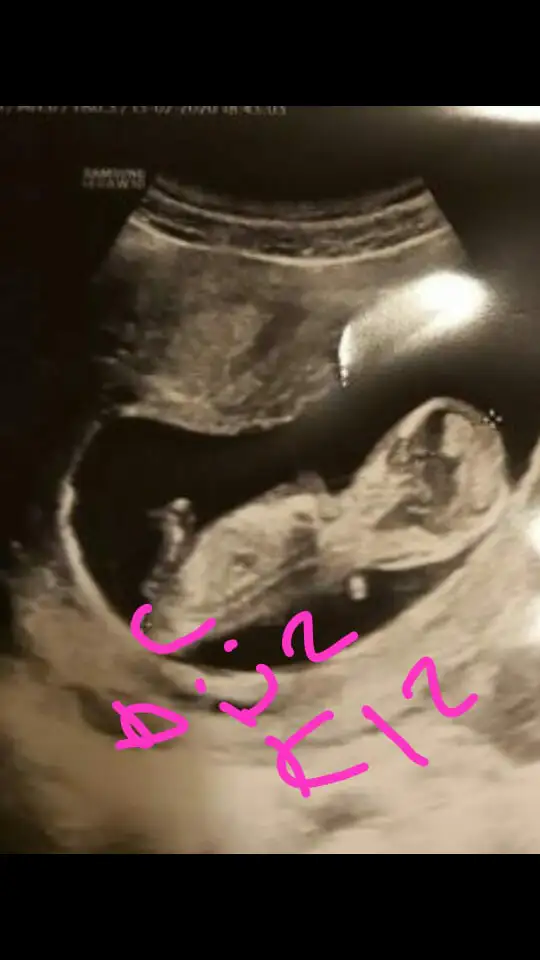

@ıkrameyra tahminin doğru çıktı kızım geliyorçok sağol

İlk zaman demiştim kız diye saglıkla gelsin prenses anketimi oylarsanız sevinirim 😊 insttagramdakinş boş ver kız dedim üzülüyordun usg ler net oldumu tahminlerde tutuyor 😊

BeratBatuhanMeva BeratBatuhanMeva Banada instagramdaki erkek demişti ama tutmadı🤩